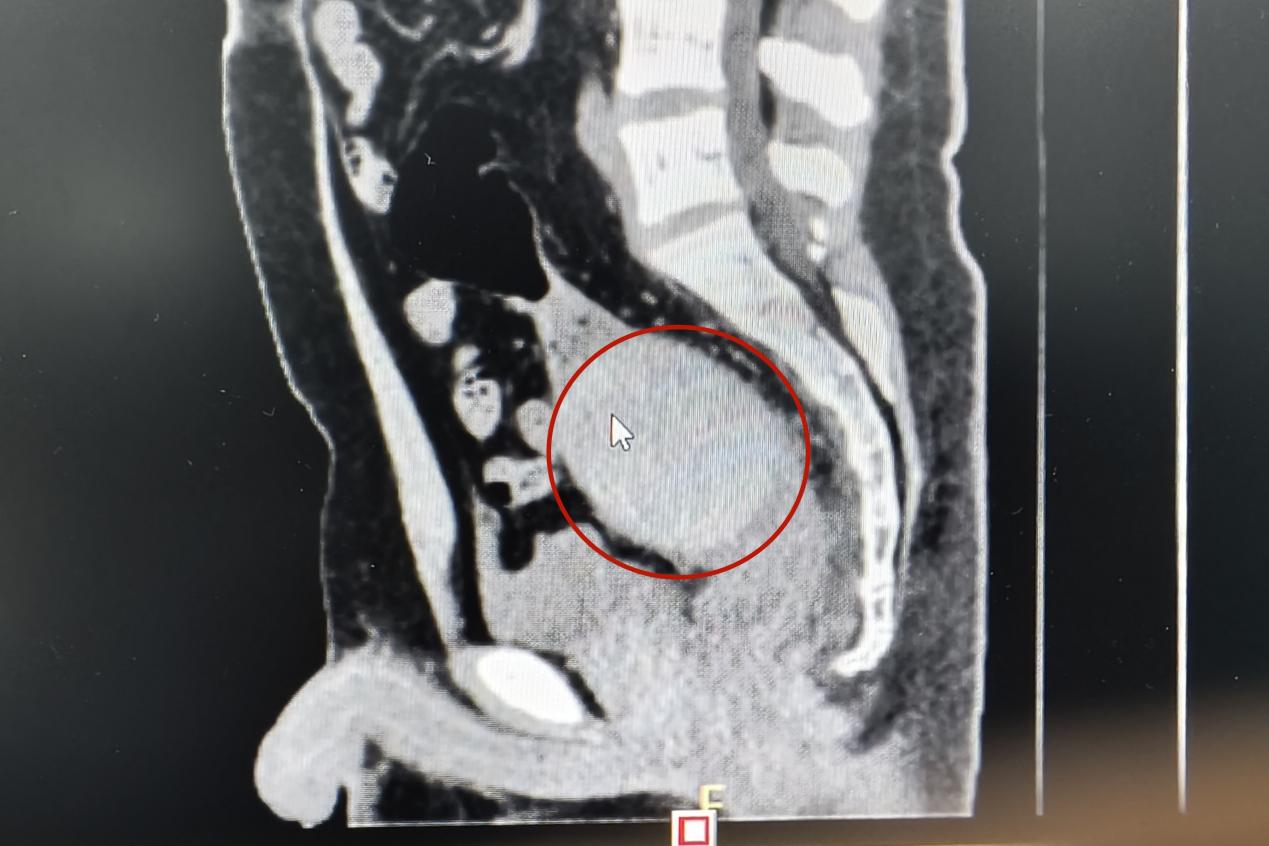

當(dāng)天下午,一名青年男子來(lái)到衡陽(yáng)市中心醫(yī)院肛腸外科門診就醫(yī),稱肛門內(nèi)有異物,肚子疼得很。李祥樂(lè)仔細(xì)詢問(wèn)病情,男子卻總是支支吾吾。看他表情痛苦,李祥樂(lè)便讓他躺到治療床上,對(duì)其進(jìn)行了肛門指檢。“你這個(gè)異物卡得很深,指檢觸不到,需要馬上做個(gè)CT明確位置?!崩钕闃?lè)一邊告知患者一邊詢問(wèn),“這個(gè)東西卡進(jìn)去多久了?”得知是昨晚發(fā)生的事,李祥樂(lè)心頭一驚,卻表面平和地安慰患者道:“沒(méi)事的,到醫(yī)院來(lái)你就放寬心了,等檢查結(jié)果出來(lái)我們想辦法給你取”。CT結(jié)果顯示患者異物位于直腸與乙狀結(jié)腸交界處,位置特殊,加之卡頓時(shí)間長(zhǎng),取的過(guò)程中腸道破裂出血的風(fēng)險(xiǎn)隨之增加。“我可以嘗試給你經(jīng)肛門取,但是如果取不出來(lái)那就需要進(jìn)行腹腔手術(shù)了”。